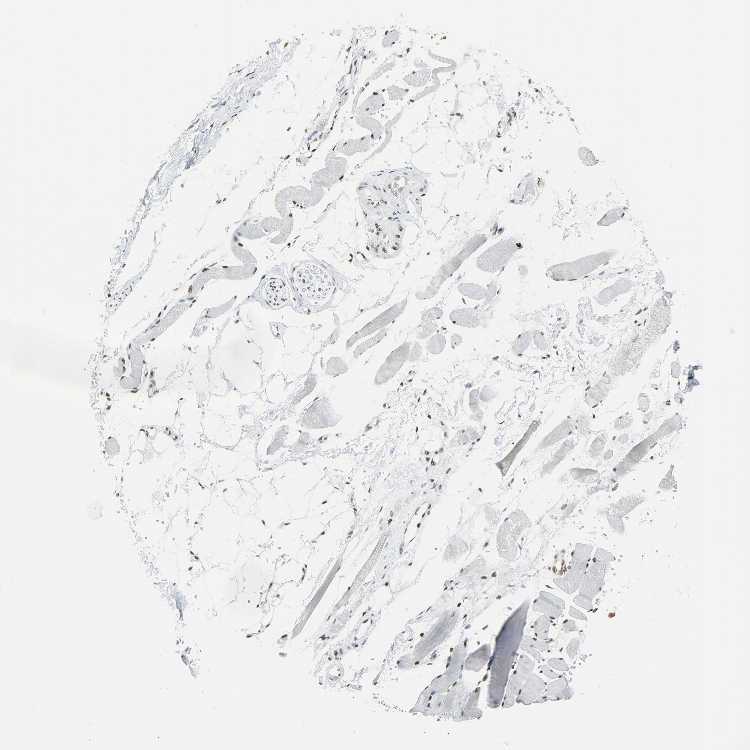

SKELETAL MUSCLE - Antibody stainingi

Antibody staining in the annotated cell types in the current human tissue is reported as not detected, low, medium, or high, based on conventional immunohistochemistry profiling in selected tissues. This score is based on the combination of the staining intensity and fraction of stained cells.

Each image is clickable and will lead to virtual microscopy that enables deeper exploration of all samples and also displays staining intensity scores, fraction scores and subcellular localization as well as patient and tissue information for each sample.

Antibody HPA046440Antibody CAB004652

Myocytes MediumHigh